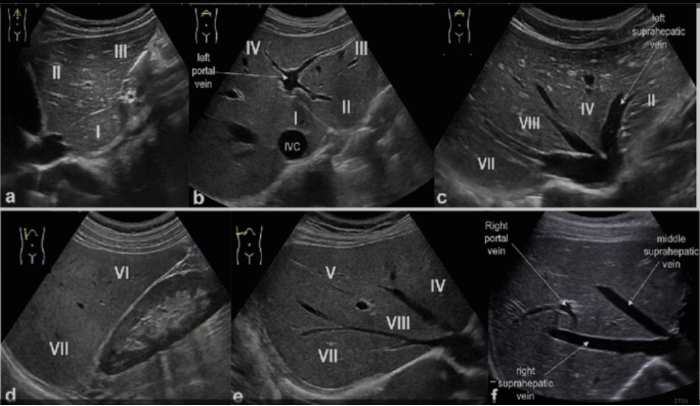

3) Hepatic segmental anatomy(간의 분절 해부학)

S1 caudate lobe (미상엽)

S2 superiolateral segment (좌외측 상구역)

S3 inferiolateral segment(좌외측 하구역)

S4 medial segment(좌내측 구역)

S5 anteroinferior segment(우전측하구역)

S6 posteroinferior segment(우후측하구역)

S7 posterosuperior segment(우후측상구역)

S8 anterosuperior segment(우전 측 상구역)

ⓐhepatic vein

left hepatic vein:간의 좌엽을 내측구역(S4)과 외측구역(S2, S3)으로 분리

middle hepatic vein: 간의 좌엽과 우엽을 분리

right hepatic vein:간의 우엽을 전구역(S5, S8)과 후구역(S6, S7)으로 분리